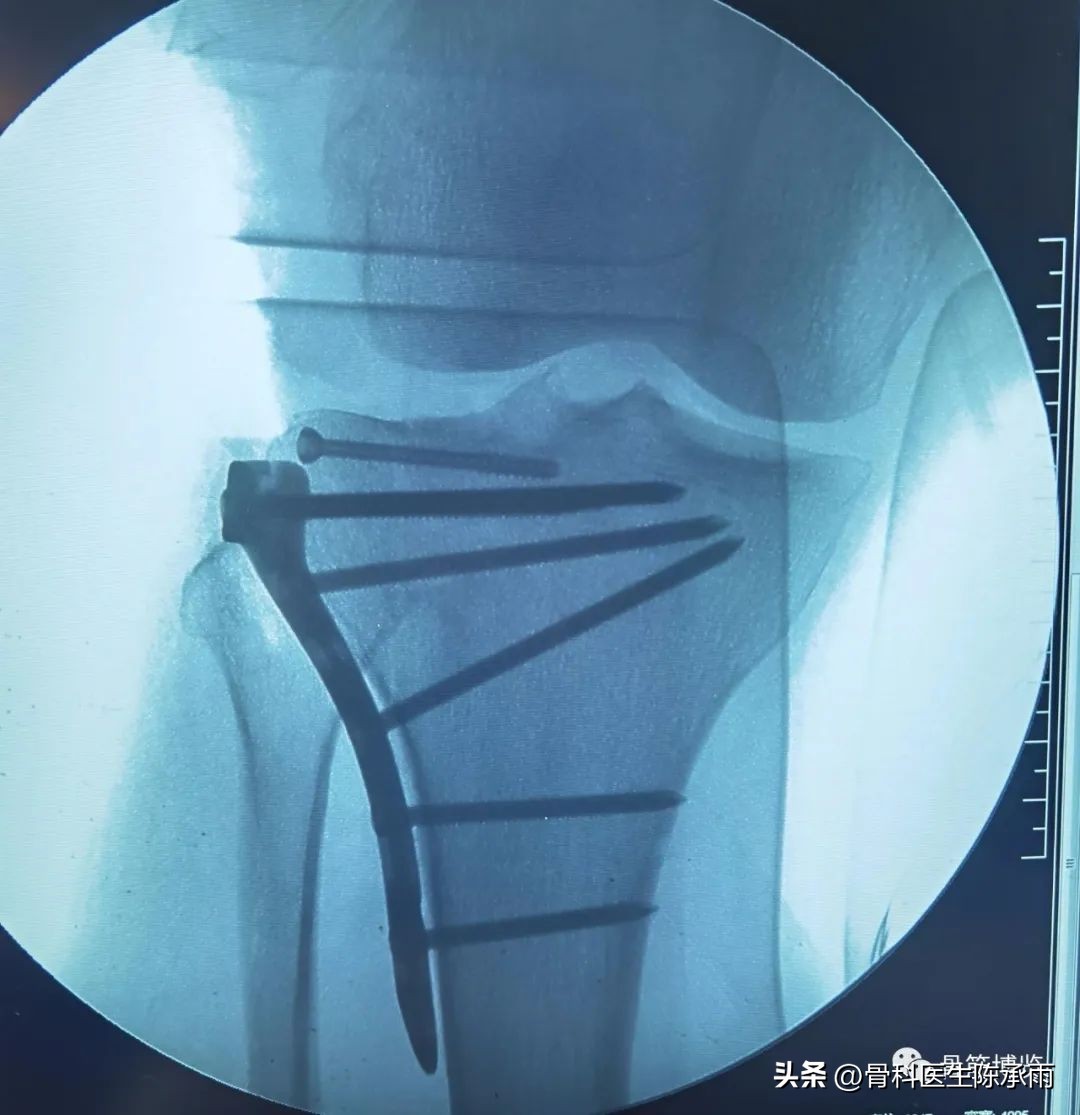

1例

2例

3例

4例

5例

6例

7例